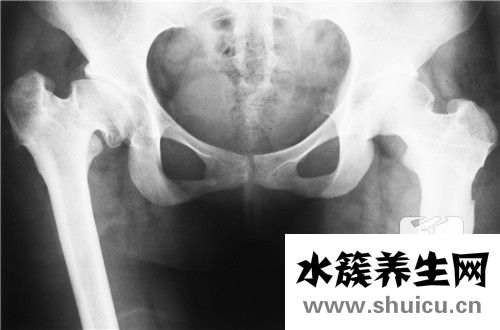

由于強烈的對撞碰撞,很少發生髖關節脫位,許多人患有先天性髖關節脫位。 先天性髖關節屬于四肢畸形,可能發生股骨頭壞死和關節僵硬等術后并發癥。 由于treatment突在治療過程中被嚴重擠壓,下肢及其肱...